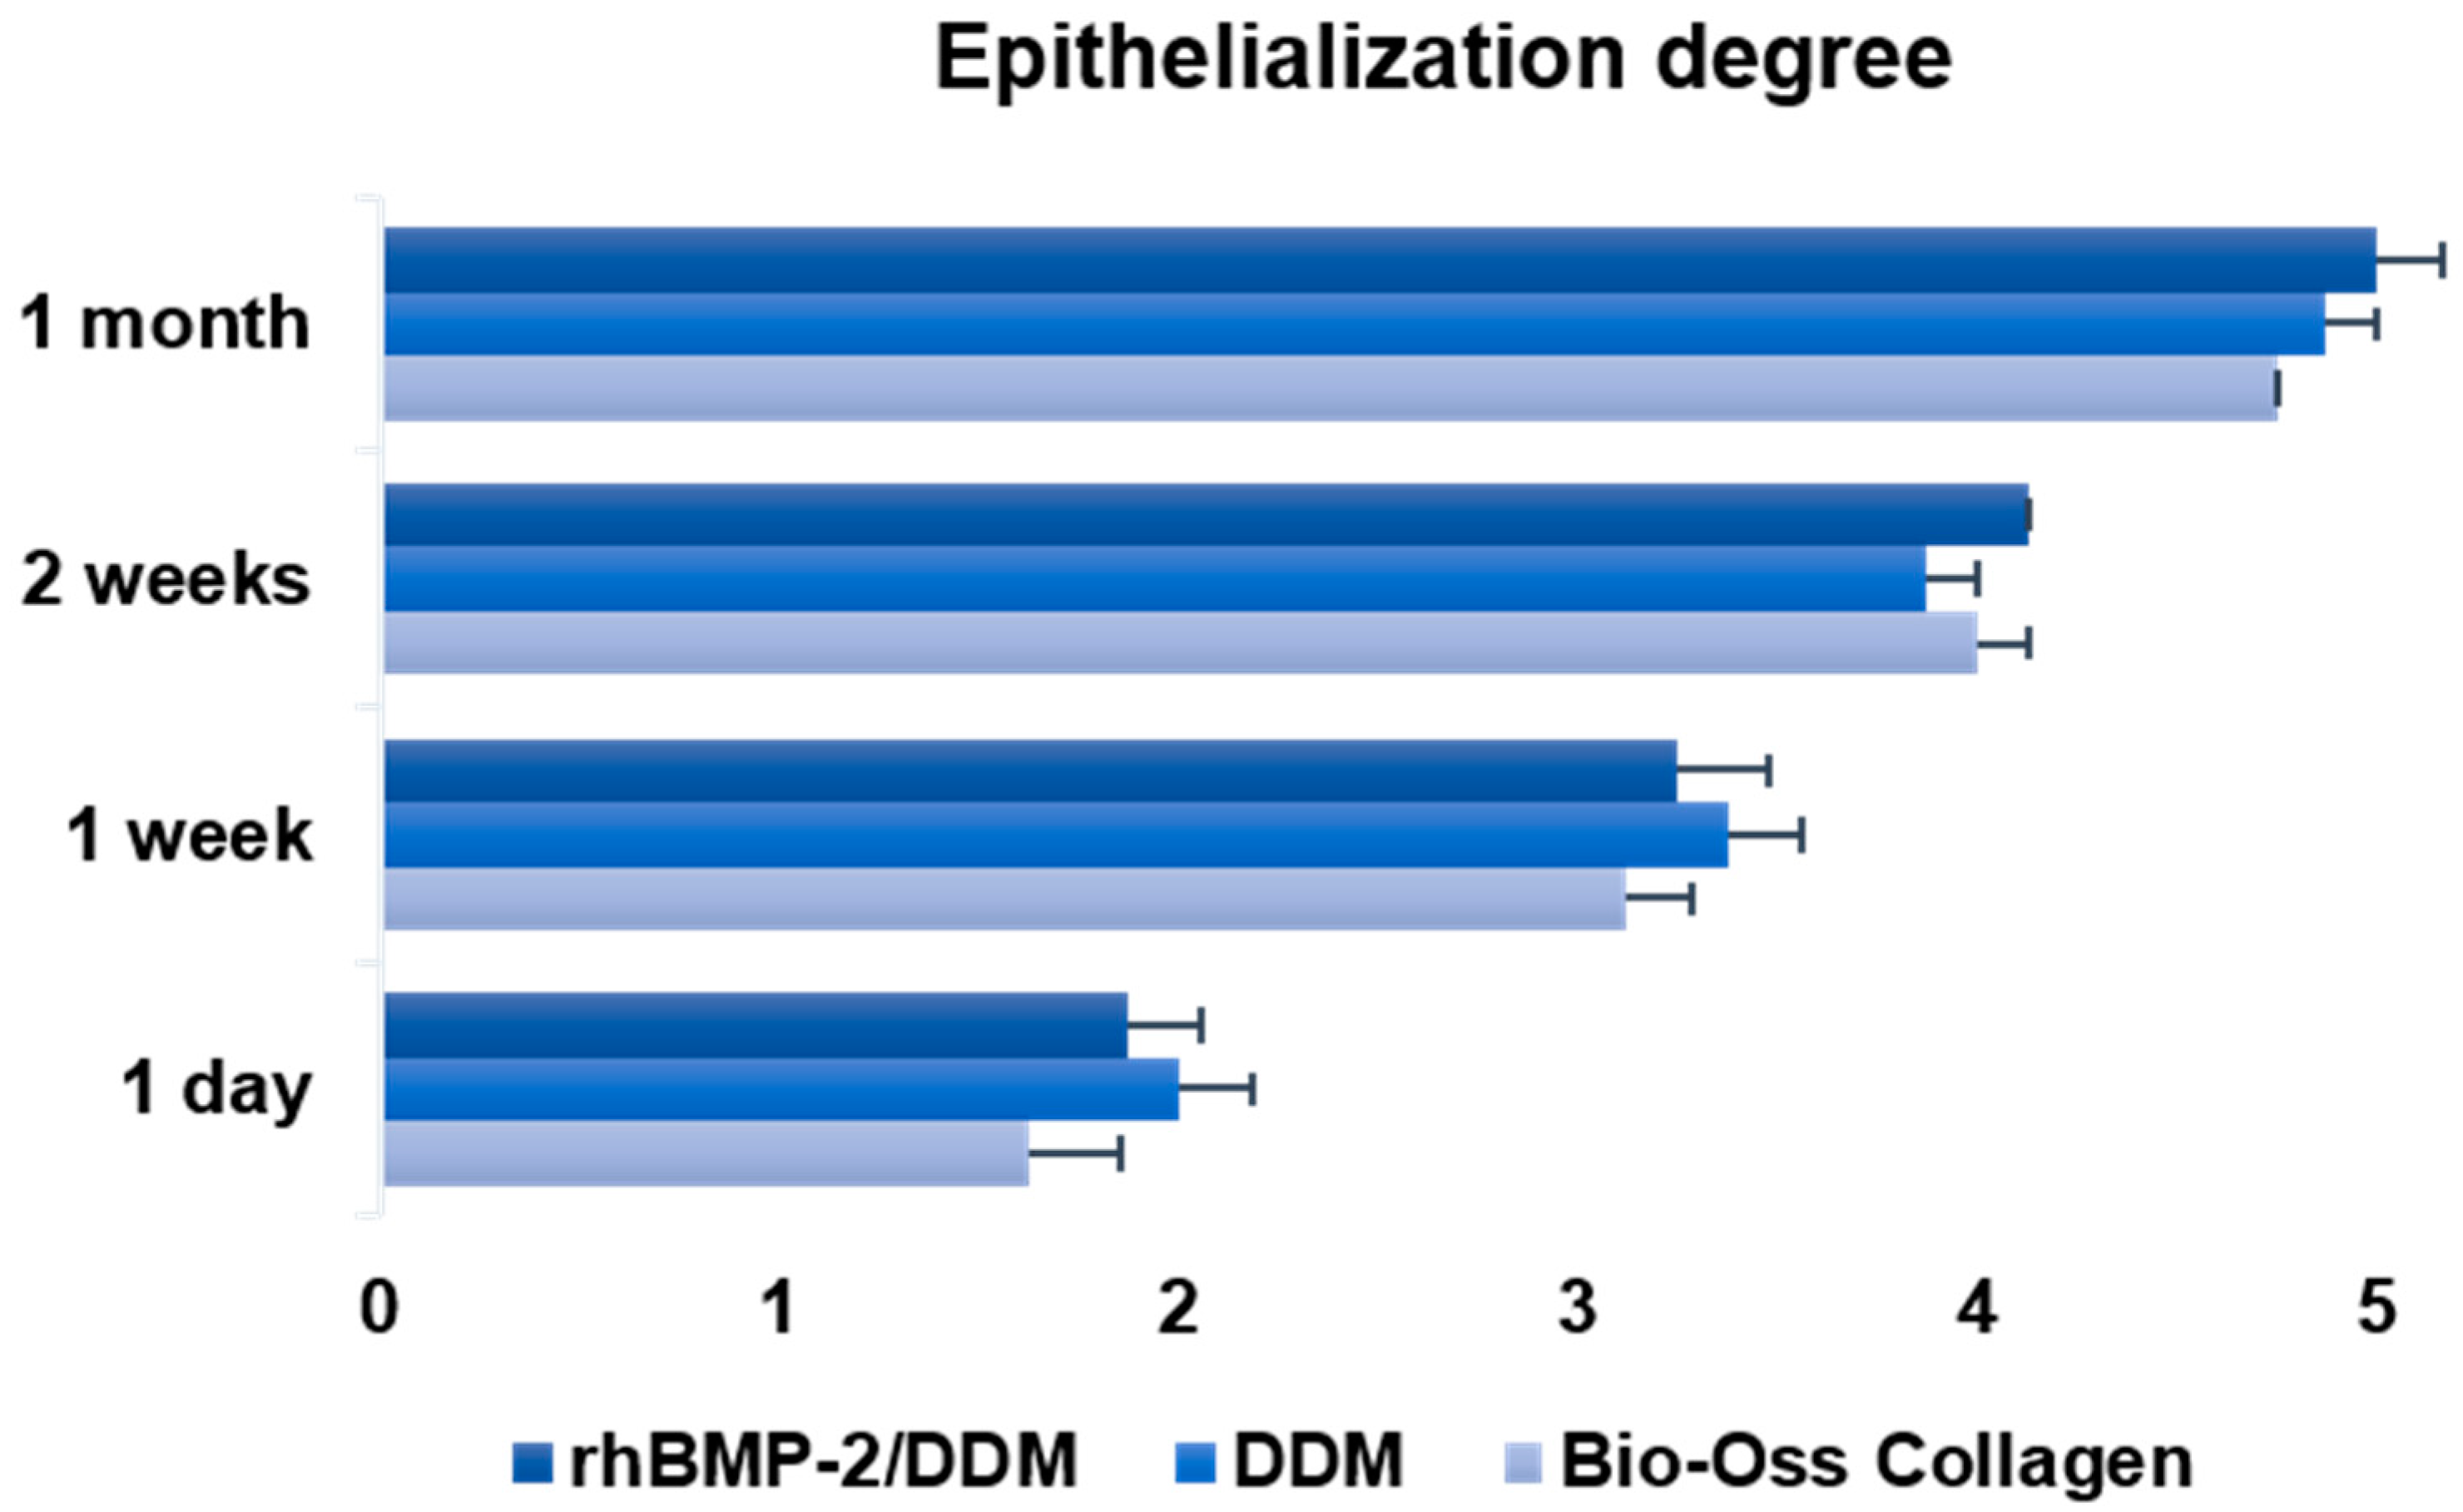

2.5. Clinical Assessment of Epithelialization

- Grade 1: non-existent

- Grade 2: covering less than one-quarter of the wound surface

- Grade 3: covering less than half the wound surface

- Grade 4: covering more than three-quarters of the wound surface

- Grade 5: normal or complete covering of the wound

3.1. Ostoperative Healing Assessment